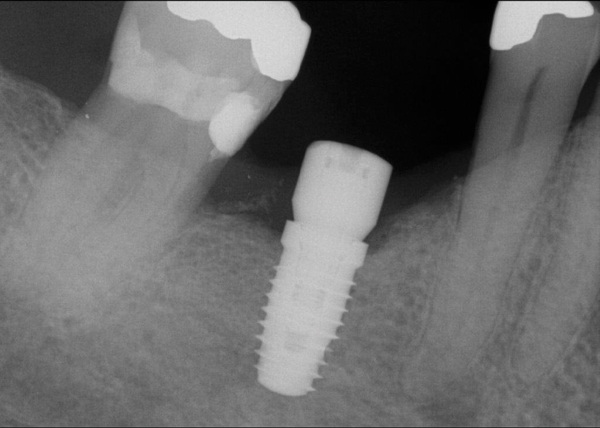

Fig 20. (Case 4) Radiograph of tooth No. 30, which had a hopeless prognosis.

Figure 20

Fig 21. Radiograph of extraction socket. Buccal plate was two-thirds resorbed.

Figure 21

Fig 22. Bone graft was placed in the socket and a d-PTFE barrier was used to cover the graft. The bone graft material was placed beyond the alveolar housing to accommodate shrinkage of graft material and to facilitate attaining a wide alveolar ridge. The barrier was removed after 5 weeks.

Figure 22

Fig 23. Implant inserted in a regenerated ridge after 6 months healing.